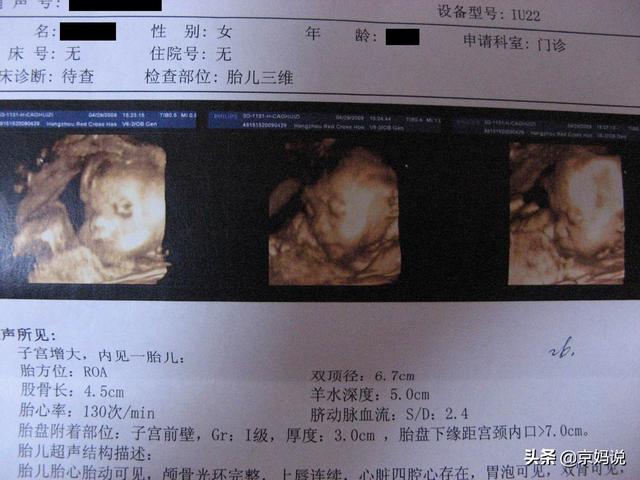

双顶径(BPD)、枕额径(OFD)、股骨长(FL)、肱骨长(HL)、头围(HC)、腹围(AC)、脐带血流比值(A/B)、胎位(LOA)、AMN-羊水等。

1. 双顶径

指的是“胎头从左到右的最长部分”,也叫“胎头大横径”

作用:主要是用来推测胎儿的体重和发育状态,孕晚期判断是否存在头盆不对称的情况是否可以顺利分娩。

孕7月时胎头双顶径是7.24-7.65cm,足月分娩时可达到9.3cm或者以上,我儿子当时就是脑袋大,出生时双顶径是9.9cm,差点没生出来。

3. 股骨长

指的是“胎儿大腿的长度”,也叫“大腿骨长”,这是胎儿身体中最长的一部分的数值。

作用:通常用于和双顶径一起来 推算胎儿的体重

它的正常值与相应的怀孕月份的双顶径值相差2-3cm,比如双顶径为9.3cm,股骨长就是7.3cm;双顶径为8.9cm,股骨长就是6.9cm。

9. AMN-羊水

这是羊水的数值,主要用来判断羊水量的多少,而羊水值的判断方法有两种,如下:

MVP:指的是最大羊水池垂直深度2-8cm为正常,超过8cm就是羊水过多、少于2cm就是羊水过少。

AFL: 指的是羊水指数,是以孕妇的脐部为中心,分上、下、左、右4个区域,将4个区域的羊水深度相加就得到羊水指数,怀孕晚期羊水指数的正常值是8-20cm,超过20cm就是羊水过多,少于8cm就是羊水过少。

关于胎头: 轮廓完整为正常,缺损、变形为异常,脑中线无移位和无脑积水为正常。

关于胎心:正常胎心频率是120-16次/分钟,有且强为正常,无且弱为异常。

关于胎盘:胎盘的正常厚度为2.5-5cm,处于子宫壁上,胎盘成熟度分为III级,0级表示胎盘发育还没成熟;I级为胎盘成熟的早期,回声均匀;II级表示胎盘接近成熟;III级表示胎盘已经成熟,越接近预产期胎盘就越成熟,回声越不均匀。